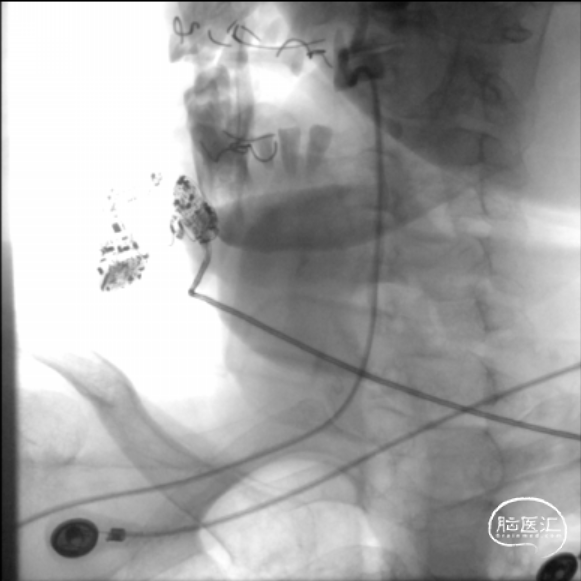

术前DSA影像:

右侧桡动脉穿刺置动脉鞘,泥鳅导丝配合6F 115cm Valent®颅内支撑导管内嵌行至右侧锁骨下动脉近右侧椎动脉起始段处,将导丝配合中间导管上行至椎动脉V3段,撤出泥鳅导丝,手推造影,显示:基底动脉中段可见重度狭窄,狭窄率约80%。